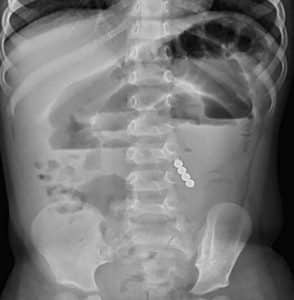

A previously healthy 3-year-old girl was presented to the emergency unit with symptoms of repeated vomiting, sweating, unable to stand, anxiety, and altered consciousness. Upon examination, she was found to be in shock, with a heart rate of 220 beats per minute, respiratory rate of 53 breaths per minute, and blood pressure of 80/44 mmHg. The abdomen was tense and grossly distended, and bowel sounds were absent. An initial abdominal radiography revealed bowel dilatation with multiple air-fluid levels and the presence of four circular radiopaque opacities in the bowel (Figure 1). The patient was admitted to the pediatric intensive care unit for resuscitation and was stabilized through intravenous fluids and ionotropic support. An emergency laparotomy was performed, which revealed a small bowel obstruction with multiple perforations. Approximately 8 inches of small bowel were resected, and end-to-end anastomosis was conducted. During the procedure, four magnetic beads, measuring 4 mm × 4 mm in size, were discovered (Figure 2). Postoperative recovery was uneventful. Retrospective questioning of the parents revealed a suspicious history of magnetic bead ingestion (Figure 3).

Figure 1: Scout abdominal film showing multiple air fluid levels with four circular radiopaque opacities in the bowel, suspicious of FB